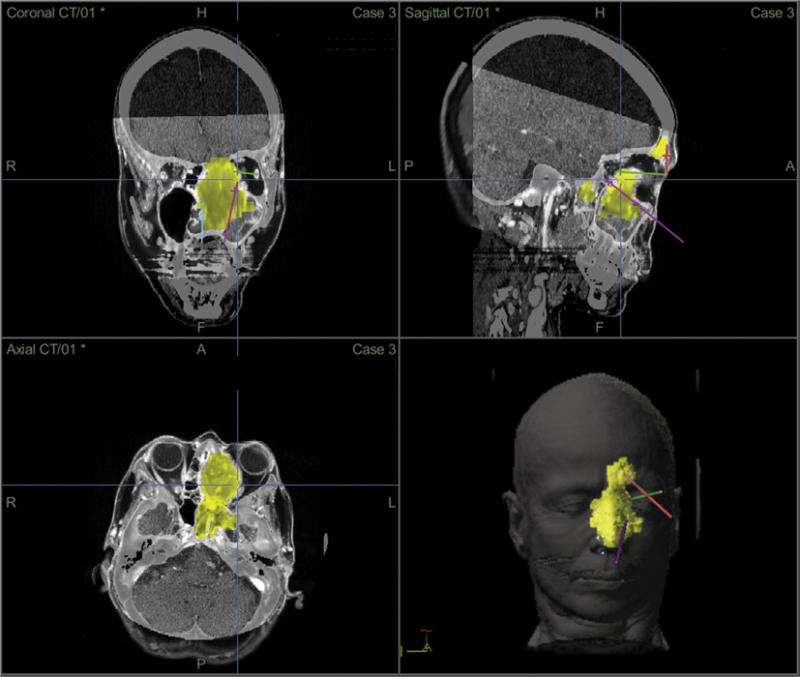

Fig. 5.

Patient 3. Preoperative coronal, sagittal and axial CT views, as well a reconstructed surface view with colorized tumor model of the sinonasal melanoma and trajectory planning through the transnasal and transorbital routes.

Preoperatively, the imaging were used to plan the most efficient pathways for tumor access using computer guided trajectory planning [17]. The patient underwent a combination of endoscopic transnasal surgery as well as endoscopic transorbital surgery through a LRC approach. Removal of the mass was completed using standard endoscopic transnasal equipment. The left olfactory nerve was infiltrated with tumor and thus resected. Margins of the resection, including periorbita, were negative for tumor on final pathology. The dura was repaired using irradiated cadaveric dermis and fibrin glue. The patient underwent neutron beam therapy to the tumor bed with Gamma Knife radiosurgery (Elekta AB, Stockholm, Sweden) to the margins.

During follow-up the patient had no visual complaints, objective abnormalities on examination or evidence of CSF leak. MRI revealed a gross total resection of tumor (Fig. 6). At 12 months, she has not developed local recurrence but did develop spinal metastases.